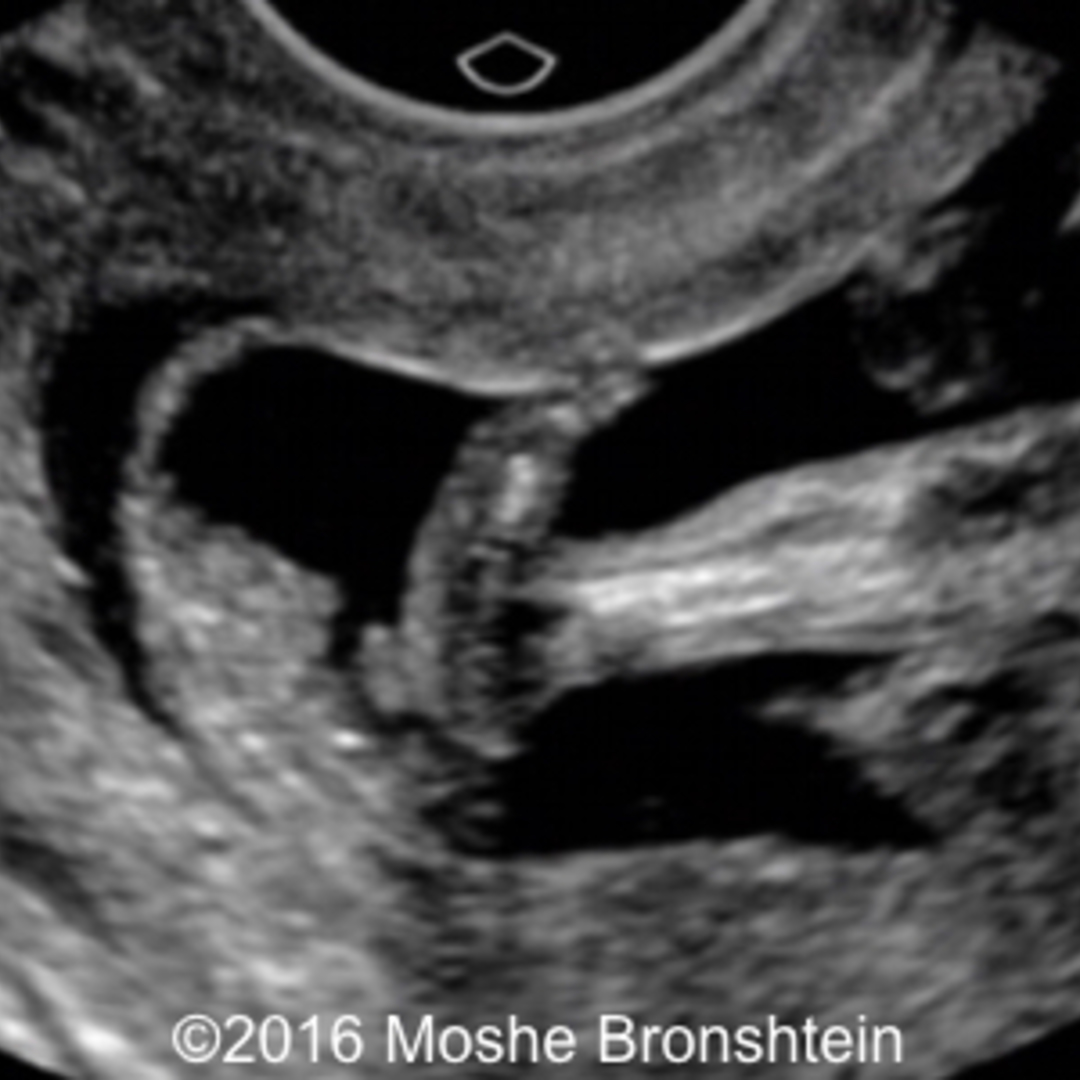

From thefetus.net

📃 Trisomy 9, rocker bottom foot Medical Term For Rocker Bottom Feet Congenital vertical talus is a rare congenital foot deformity in which the sole of a child’s foot flexes abnormally in a convex position giving the foot. Congenital vertical talus, commonly referred to as rocker bottom foot, is a rare foot deformity present at birth. More advanced charcot foot can cause changes to your foot’s shape (charcot foot deformity), including: Congenital. Medical Term For Rocker Bottom Feet.